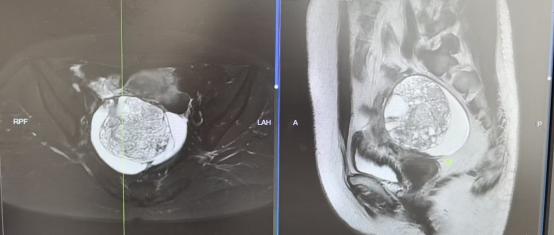

这次因为腹痛加剧来院,检查发现她的巧囊不仅巨大,囊壁还出现了丰富的乳头样实性突起。术后病理证实了我们的担忧:她的“子宫内膜异位囊肿”已经恶变为卵巢透明细胞癌。

术前核磁影像